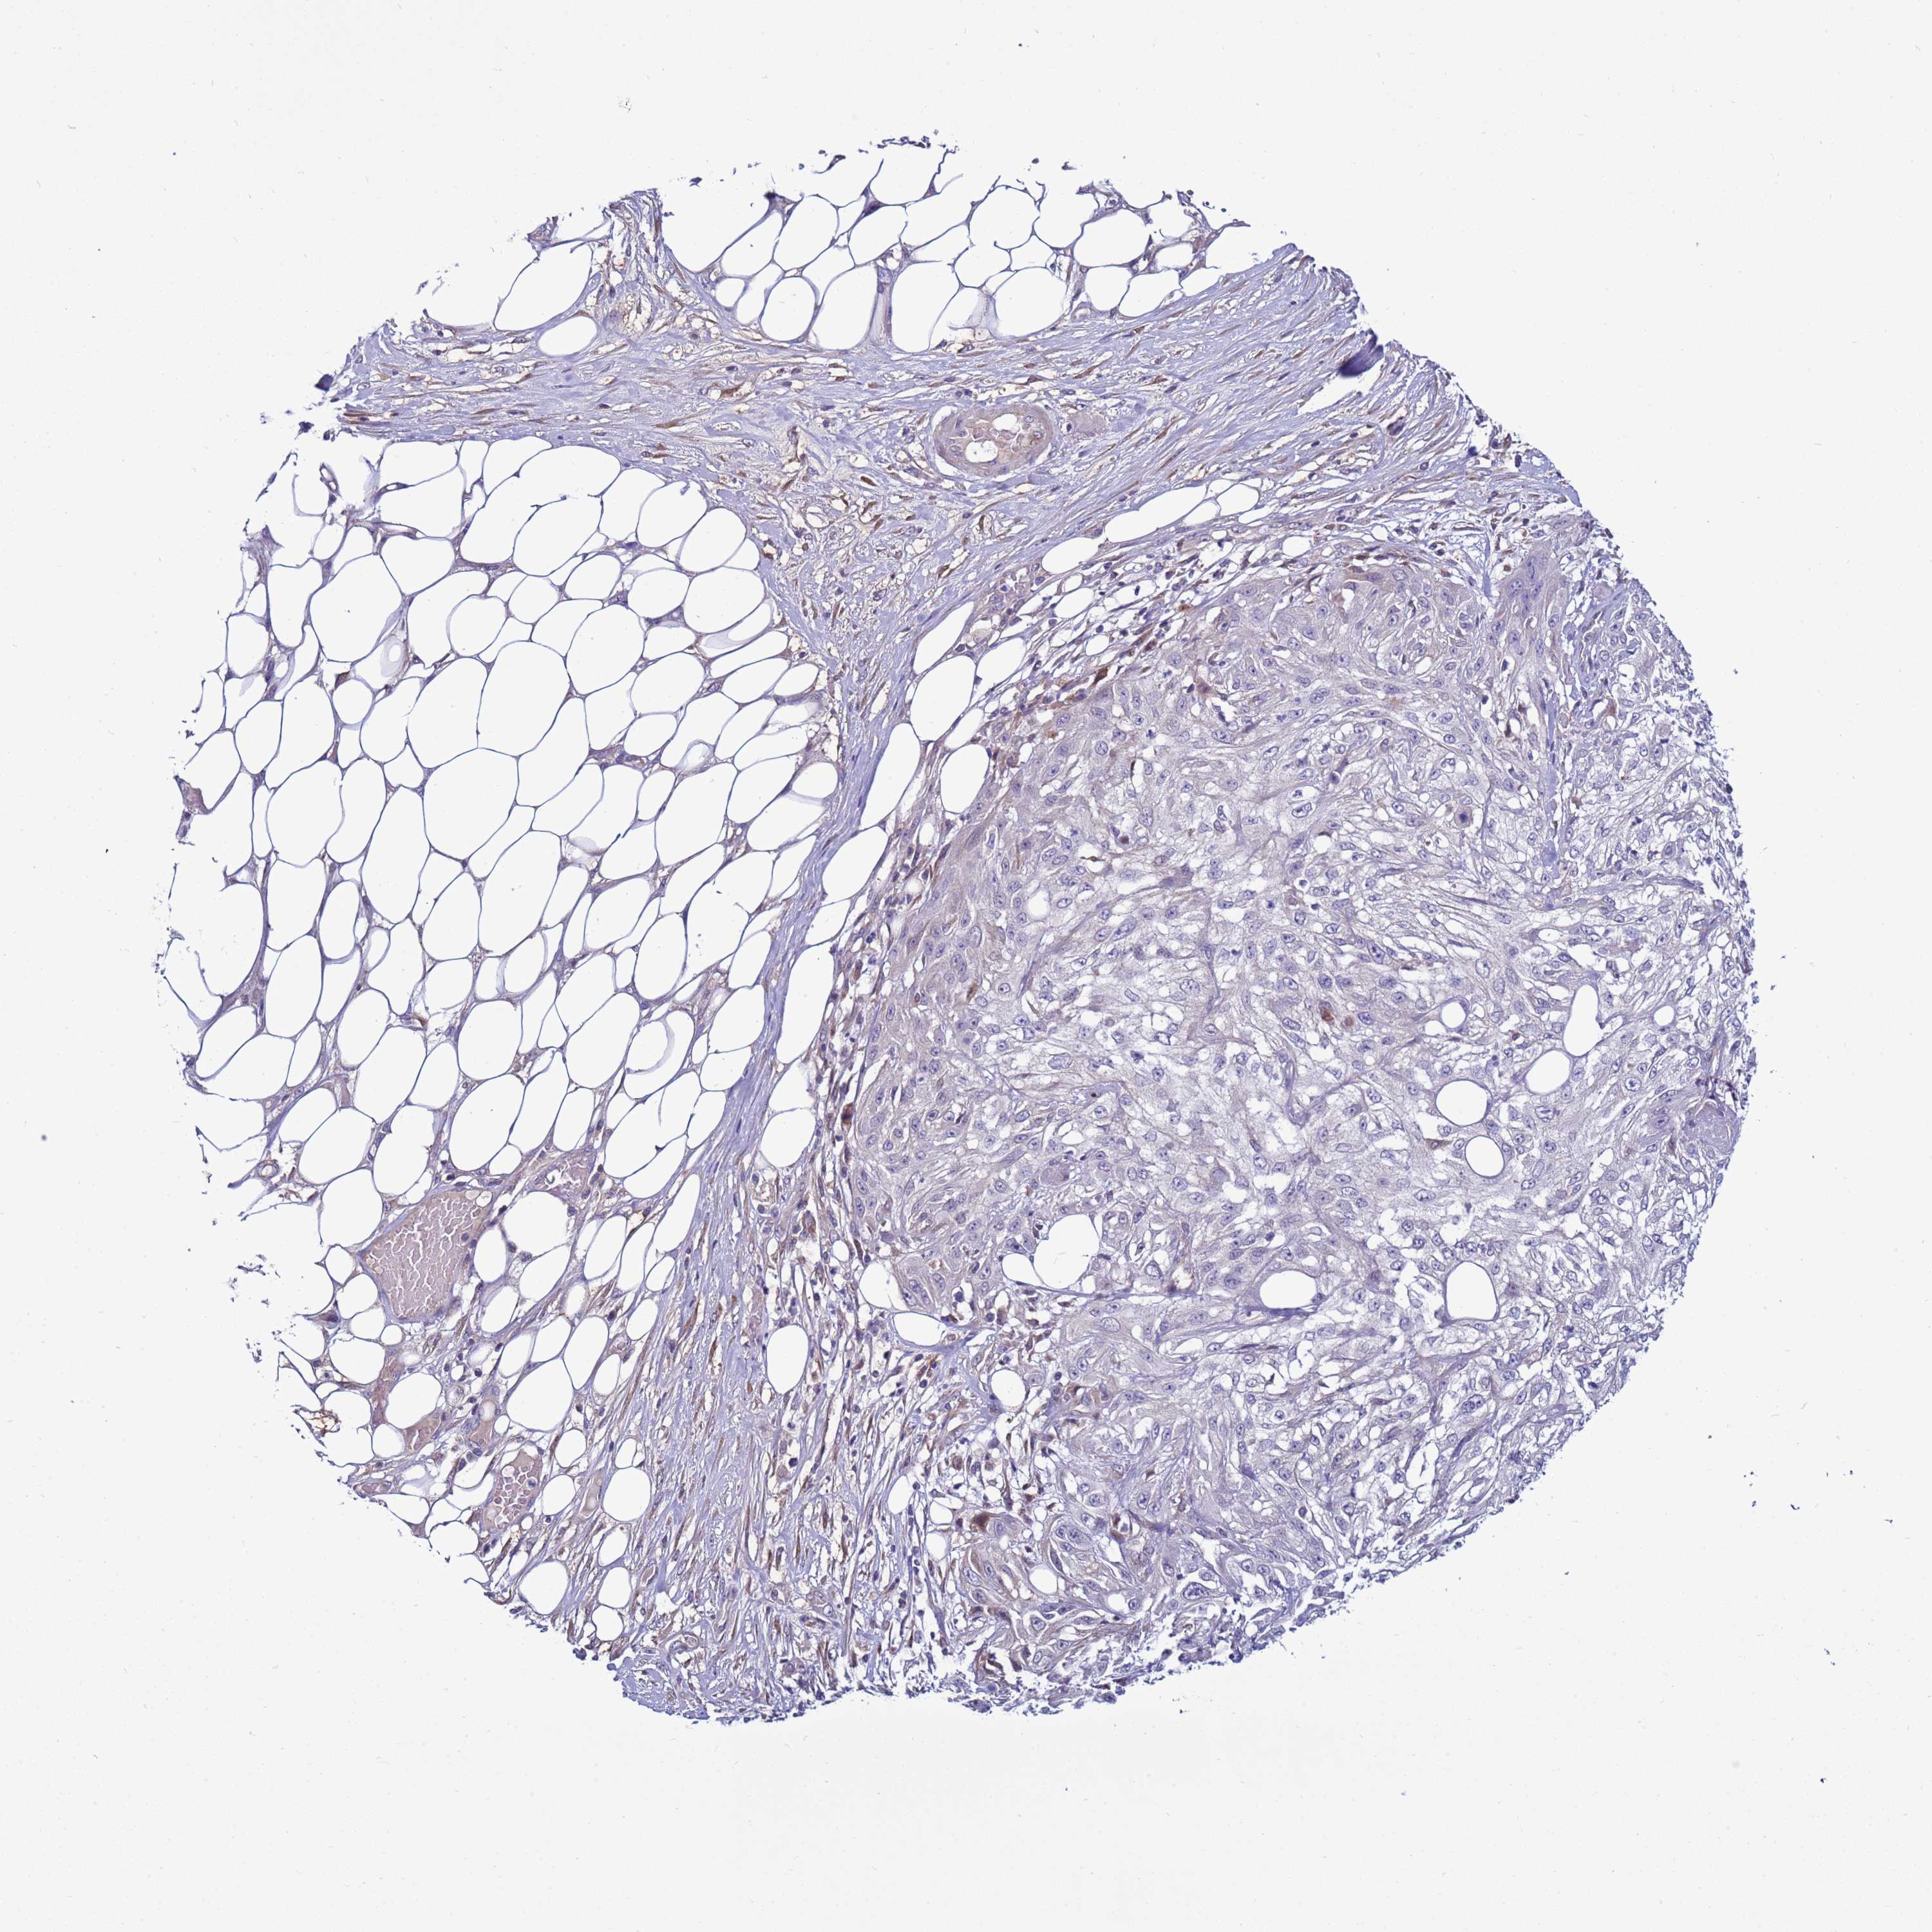

SKIN CANCER - Protein expressioni

A mouse-over function shows sample information and annotation data. Click on an image to view it in a full screen mode. Samples can be filtered based on level of antibody staining by selecting one or several of the following categories: high, medium, low and not detected. The assay and annotation is described here.

Antibody stainingi

Antibody staining in the annotated cell types in the current human tissue is reported as not detected, low, medium, or high, based on conventional immunohistochemistry profiling in selected tissues. This score is based on the combination of the staining intensity and fraction of stained cells.

Each image is clickable and will lead to virtual microscopy that enables deeper exploration of all samples and also displays staining intensity scores, fraction scores and subcellular localization as well as patient and tissue information for each sample.

Antibody HPA043704

Basal cell carcinoma